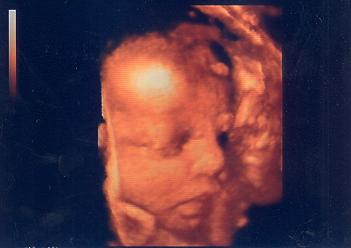

Azért az még koraszülött! Ha bennem elfért, benned is el fog (153 cm!)!!!!!